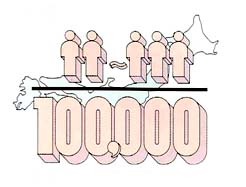

脳下垂体には数種類の腫瘍が発生しますが、その大半は腺腫(アデノーマ)と呼ばれる良性の腫瘍です。一般に、脳腫瘍は年間10万人に15例程度発生するといわれています。その約17%が脳下垂体腺腫ですから、この腫瘍の年間発生率は入口10万人に2〜3 例ということになります。つまり入口約1,000万の東京では、年間約250例の下垂体腺腫が発生することになります。